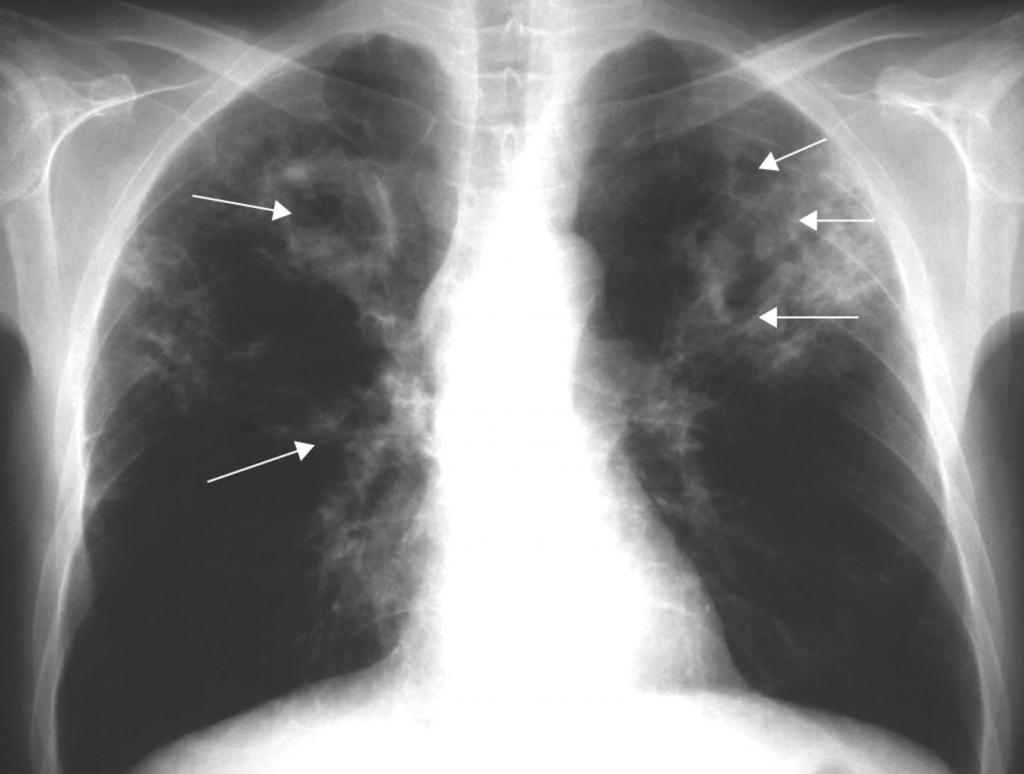

На рентгенограмме обнаруживается при туберкулезе:

- Диссеминированном. Множество мелких, хорошо очерченных, или более крупных пятен, есть каверны.

- Очаговом. Уплотнение находится не ниже 2 ребра, вокруг могут быть фиброзные тяжи, усилен легочный рисунок.

- Инфильтративном. Уплотнения правильной округлой формы на рентгеновском снимке в верхней легочной доле.

- Казеозной пневмонии. Множество полостей распада с неровными краями, очагами отсева, смещением средостения в больную сторону груди.

Инфильтраты при туберкулезе зависят от формы данного заболевания:

- Диссеминированный туберкулез сопровождается множественными мелкими очагами до 2 мм в диаметре,

- Очаговый , имеет один или несколько теней округлой, эллиптической, реже вытянутой формы с низкой интенсивностью, при которой очаги поражений темнее костной ткани,

- Казеозная форма является самой тяжелой и сопровождается затемнением нескольких долей или даже целого легкого, тень изменяется по мере распада от менее интенсивной до более выраженной,

- Кавернозный , характеризуется очаговым затемнением с просветом посередине (каверна).

Диссеминированная форма

Эту форму туберкулеза можно поделить на острую, подострую и хроническую. Как правило, развивается остро со стремительным распространением туберкулезных палочек по всему организму.

То, как выглядит туберкулез на снимке, зависит как от характера его распространения, так и от остроты процесса. Наиболее характерный подтип диссеминированного туберкулеза — милиарный туберкулез. Он представляет собой острую, чаще всего гематогенную инфекцию.

Ниже перечислены основные его признаки на рентгене:

- большое количество мелких очагов, несколько миллиметров в диаметре;

- очаги равномерно распространены по всему легочному полю;

- иногда очаги сливаются;

- корни легких несколько приподняты;

- иногда объем легочной ткани становится меньше.